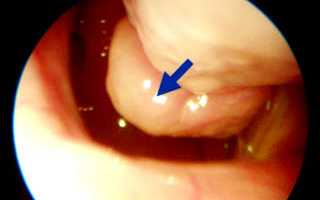

Основным и наиболее эффективным способом диагностики является эндоскопия. Этот метод позволяет точно определить степень и локализацию патологического процесса.

При ринодиагностике наблюдается гиперплазия (утолщение) слизистой оболочки нижнего отдела носа, реже — среднего. Измененные участки могут иметь как гладкую, так и бугристую поверхность. Слизистая оболочка выглядит покрасневшей и слегка синюшной. При утолщении костной основы носовых раковин их размеры не увеличиваются.